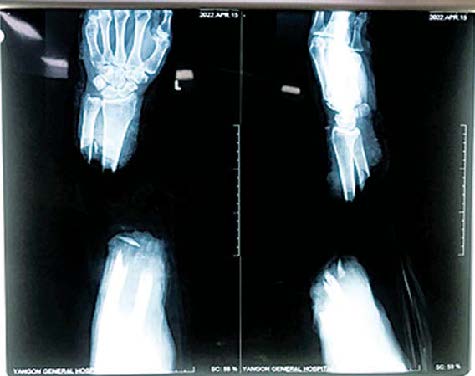

လူနာမှာ ရန်ကုန်တိုင်းဒေသကြီး ကြည့်မြင်တိုင်မြို့နယ်တွင် နေထိုင်သည့် ငါဖမ်းလုပ်ငန်း လုပ်ကိုင်သူဖြစ်ပြီး ဧပြီ ၁၄ ရက် မွန်းလွဲ ၃ နာရီတွင် ဓားဖြင့် ခုတ်ခံရခြင်းကြောင့် ဘယ်ဘက်လက်၏ လက်ကောက်ဝတ်အထက်မှ ပြတ်တောက်သွားသည့် ဒဏ်ရာ (Amputated Left Forearm) ဖြင့် ရန်ကုန် ပြည်သူ့ဆေးရုံကြီးသို့ အဆိုပါနေ့ ညနေပိုင်းတွင် ပြတ်တောက်သွား သော လက်နှင့်အတူ ရောက်ရှိလာရာ သက်ဆိုင်ရာ ဆရာဝန်များ၊ သူနာပြုများနှင့် ကျန်းမာရေး ဝန်ထမ်းများက လိုအပ်သော အရေးပေါ်ပြုစု ကုသမှုများ ပြုလုပ်ပေးခြင်း၊ လက်ပိုင်းဆိုင်ရာ ခွဲစိတ်ကုသမှု အထူးကုဆရာဝန်ကြီးများထံ အချိန်နှင့်တစ်ပြေးညီ ဆက်သွယ်ပြီး ပြတ်တောက် သွားသောလက် ပြန်လည်ဆက်နိုင်ရေးအတွက် လိုအပ်သော စမ်းသပ်စစ်ဆေးမှုများ ပြုလုပ်၍ အရေးပေါ် ခွဲစိတ်ခန်းဝင်ရန် ပြင်ဆင်ခဲ့ကြောင်း။

ခွဲစိတ်ကုသမှုကို ရန်ကုန် ပြည်သူ့ဆေးရုံကြီးမှ လက်ပိုင်း ဆိုင်ရာခွဲစိတ်ကုသမှု ပါရဂူဘွဲ့ သင်တန်းသား ဒေါက်တာဖြိုးမောင်မောင် ဦးဆောင်သည့် လက်ထောက် ဆရာဝန်(အရိုး) ဒေါက်တာမောင်မောင်လွင်၊ ဆေးပညာဘွဲ့လွန် (အရိုး) သင်တန်းသား ဒေါက်တာမင်းသူ၊ ဒေါက်တာဟိန်းပြည့်အောင်၊ မေ့ဆေးအထူးကုဆရာဝန် ဒေါက်တာထွန်းထွန်းနိုင်နှင့် အထက်တန်းသူနာပြု ဒေါ်မေသူရတို့ ပါဝင်သောအဖွဲ့က ဧပြီ ၁၄ ရက် ည ၇နာရီ မိနစ် ၅၀ မှ စတင်ဆောင်ရွက်ခဲ့ရာ ဧပြီ ၁၅ ရက် နံနက် ၁ နာရီခွဲတွင် ခွဲစိတ်ကုသမှုပြီးဆုံးခဲ့ကြောင်း သိရ သည်။

အဆိုပါ လူနာ၏ လက်မှာ ခွဲစိတ်ပြီးချိန်မှစတင်၍ သွေးကြောများ ဖြည်းဖြည်းချင်း ပြန်လည် လှည့်ပတ်စီးဆင်းလာပြီး ဧပြီ ၂၅ ရက်မှစတင်၍ အကြောအဆစ် ရောဂါကု ပညာဌာန ပြင်ပလူနာဌာနတွင် လေ့ကျင့်ခန်းများ လုပ်ဆောင်ခဲ့ပြီး ဧပြီ ၂၉ ရက်တွင် ဆေးရုံမှ ဆင်းခွင့်ပြုပြီးဖြစ်သည်။